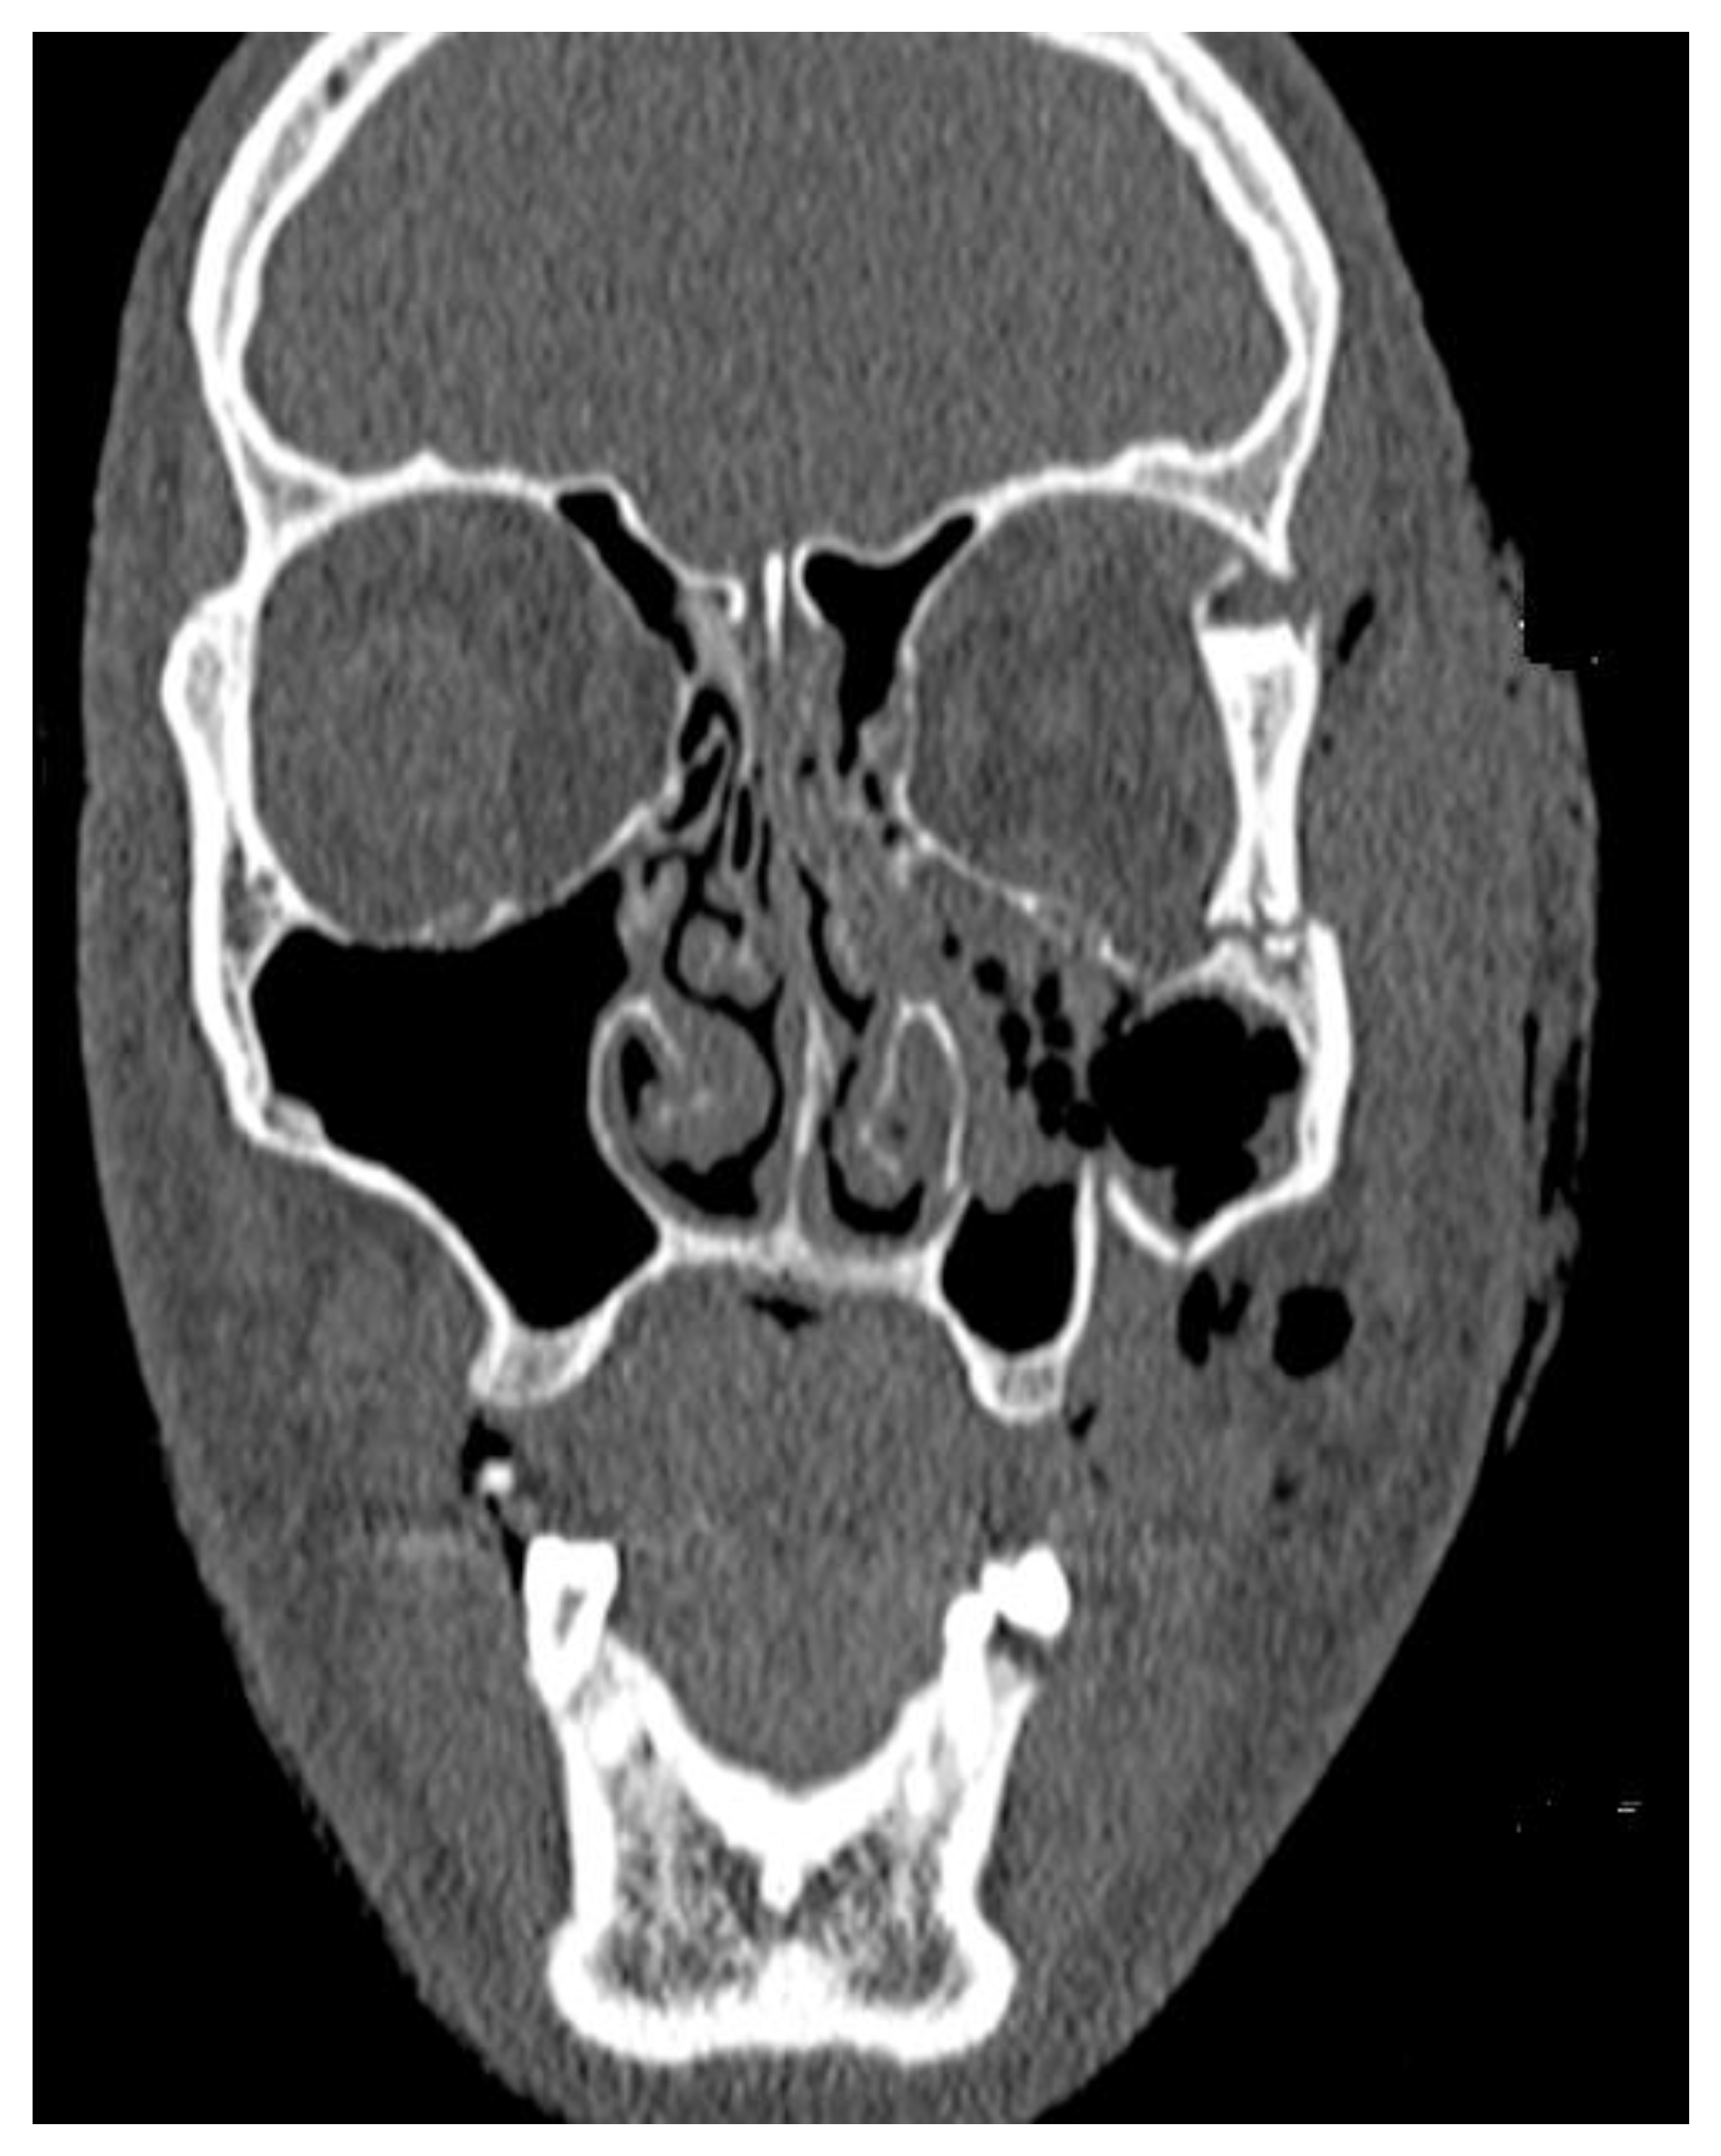

A 36 year-old male suffered from a blunt craniofacial trauma on the left temporal region caused by a baseball bat beating. The patient was admitted to the emergency department and then to the Ward of Maxillo-Facial Surgery. Because of the excessive fractures of the temporal bone along with the skull base and middle cranial fossa, the patient required intense monitoring (Figure 1, Figure 2, Figure 3, Figure 4, Figure 5 and Figure 6). Neurological status was fine; no CSF leak was present. No neurosurgical intervention to lift the displaced bone was used because of the close proximity of the meningeal artery in the fractured temporal bone region, which might cause serious, life-threatening bleeding. Secondly, the displacement was slightly less than 5 mm in total and symptomless. Detailed trauma-CT scans and 3D visualization revealed a fracture of the cranial base, along with the middle cranial fossa vault, cranial displacement of some part of the left frontal bone, and a fracture of the left zygomatic-orbital complex (Figure 7, Figure 8, Figure 9 and Figure 10).

Figure 10. Trauma CT in frontal view with visible medially displaced entire lateral orbital wall of the left eye socket and massive swelling of soft tissues. Displaced lateral walls cause a slight decrease in orbital socket volume; however, the globe remains in the same position without any exophthalmos.